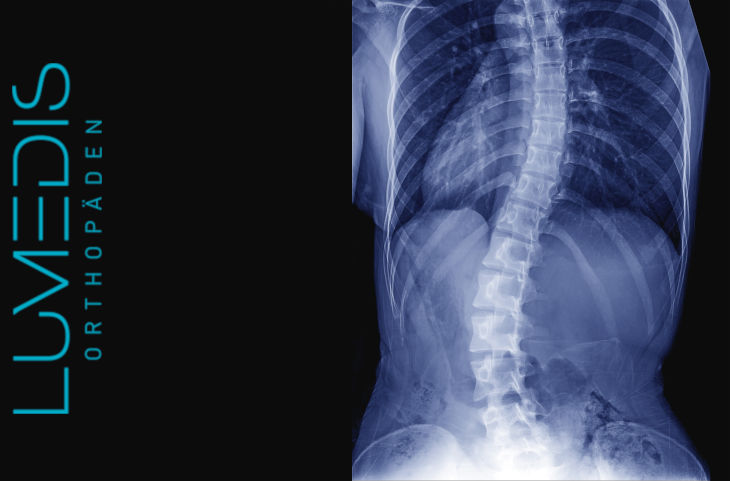

Röntgenbild einer degenerativen LWS Skoliose

Abbildung einer Skoliose mit Cobb Winkel

Abbildung Skoliose von der Seite und von hinten

MRT der LWS / BWS mit schwerer Skoliose - über die Stellung der Deckplatten

Durch türkise Linien gekennzeichnet, kann man die Skoliose gut erkennen.

Röntgenbild der gesamten Wirbelsäule mit starker Skoliose